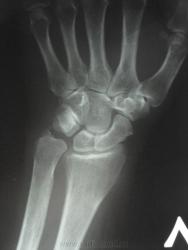

женщина, 1956 года рождения, жалобы на боли в правой лучезапястном суставе в течение полу года, травму отрицает. Кроме остеохондропатии полулунной кости в голову ничего не приходит. Ваше мнение коллеги))))))))

Скоро наступит патологический перелом...

Остеохондропатия - удел детского возраста. Здесь, думаю, правильнее говорить об асептическом некрозе.

Остеохондропатия (греч. οστεοχονδροπαθια) – асептический некроз губчатой кости, протекающий хронически и дающий осложнения в виде микропереломов. Остеохондропатии являются следствием местных расстройств кровообращения, возникающих в результате воздействия различных факторов: врождённых, обменных, травматических и др.